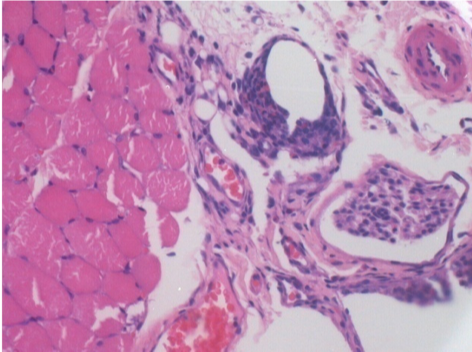

1 month after Endopeel Injection

1 month after Endopeel Injection 0.1ml in the right pretibial muscle.

What is seen in black on the pictures is not a necrosis like could imagine some scientifics !

In fact, 4 conclusions have to be taken in consideration

- an artefact of coloration

- an absence of necrosis

- an apoptosis

- a bioregenerative process

L : Control-100xD30

R:100xD30

R :400xD30